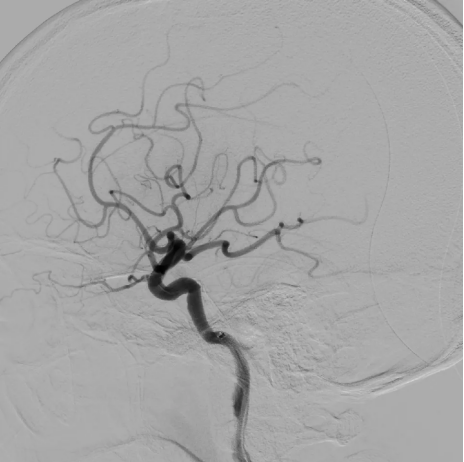

术中脑血管造影证实责任血管为左侧大脑中动脉M2上干闭塞。M2段血管取栓治疗属于MeVO取栓。

这类手术被称为“刀尖上的舞蹈”:一是M2上干管腔细小、路径迂曲,操作空间极小;二是血管壁脆弱,易破裂出血;三是若血管未及时开通,患者可能终身遗留神经功能缺损。

术中,介入医生凭借丰富的临床经验与精准的操作技巧,在纤细迂曲的血管通道中谨慎操控器械,逐步推进至血栓位置,最终成功将M2上干内的血栓取出,实现血管再通。